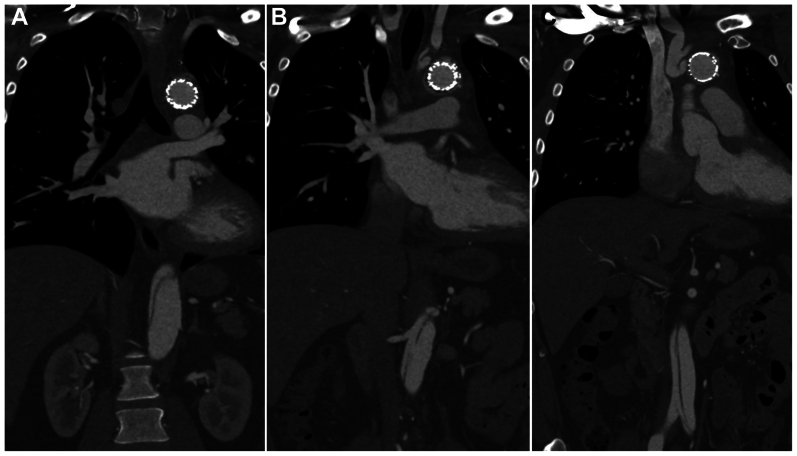

Fig 2.

Computed tomography angiogram of patient 1 demonstrating aortic dissection in the septum, distal to the frozen elephant trunk (A), at the level of the renal arteries with a large septal fenestration (B), and in the infrarenal aorta (C).